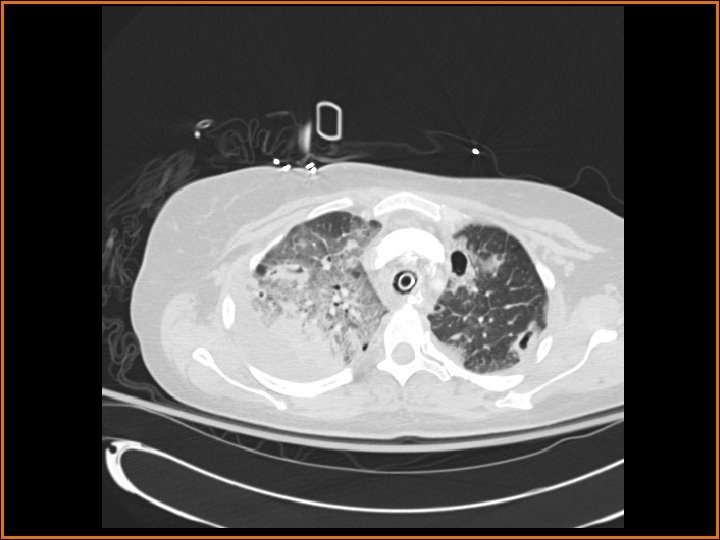

Findings and Differentials CT Findings: Multiple bilateral peripheral nodular opacities are seen, many of which are fed by arterial branches. Some of the nodules are cavitary. Diffuse bilateral ground glass opacities are seen with air bronchograms. The large lucency projecting over the right hemidiaphragm on the plain film corresponds to a pleural air collection that is directly contiguous with one of the cavities. Differential Diagnosis: • Multiple cavitary metastases • Septic Emboli

Discussion (Continued) In this patient, the large right anteroinferior pleural air collection is contiguous with one of the cavities (as seen on the second CT image) and represents a bronchopleural fistula. Etiologies of bronchopleural fistulas include necrotizing infection, active TB, irradiation, tumor in a bronchial margin, etc. If the bronchopleural fistula is large, a persistent pneumothorax with or without contralateral mediastinal shift may be present. In this case, a septic embolus had eroded into the pleural space, creating the lucent collection projecting over the right hemithorax on the plain films. Finally, the ground glass opacities represented pneumonia in this patient.

Diagnosis Septic Emboli with Bronchopleural Fistula